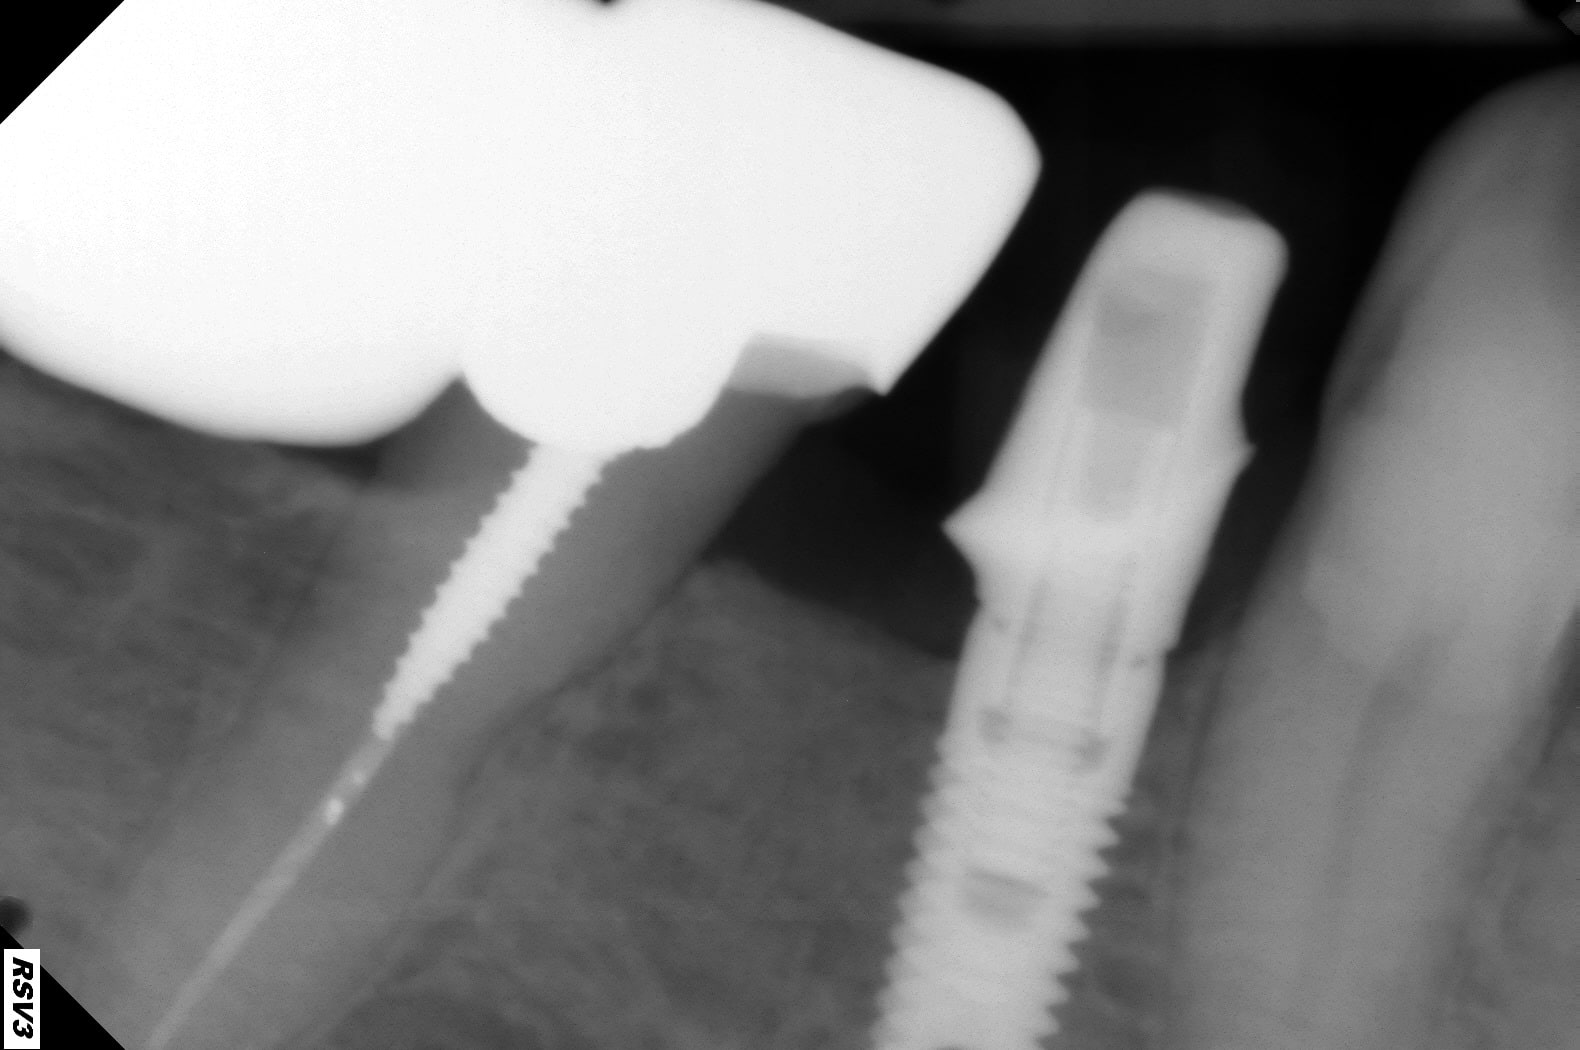

Est ce qu'avec une tibase ou un pilier classique on peut avoir un ajustement gingival comme avec un pilier usiné sur mesure?

tout dépend de ton contour gingival, de la différence de hauteur entre mésial, distal, vestibulaire et lingual.